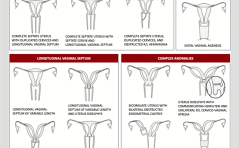

ASRM-21-Version der Müllerschen Missbildungen / Viele urogenitale Menopausensymtome bleiben unbehandelt / Statine senken Inzidenz und Mortalität gynäkologischer Karzinome / Menstruationsbeschwerden und antiretrovirale Therapie / St. nach Fehlgeburt und ... PDF DokumentFortplanzungsmedizin aktuell